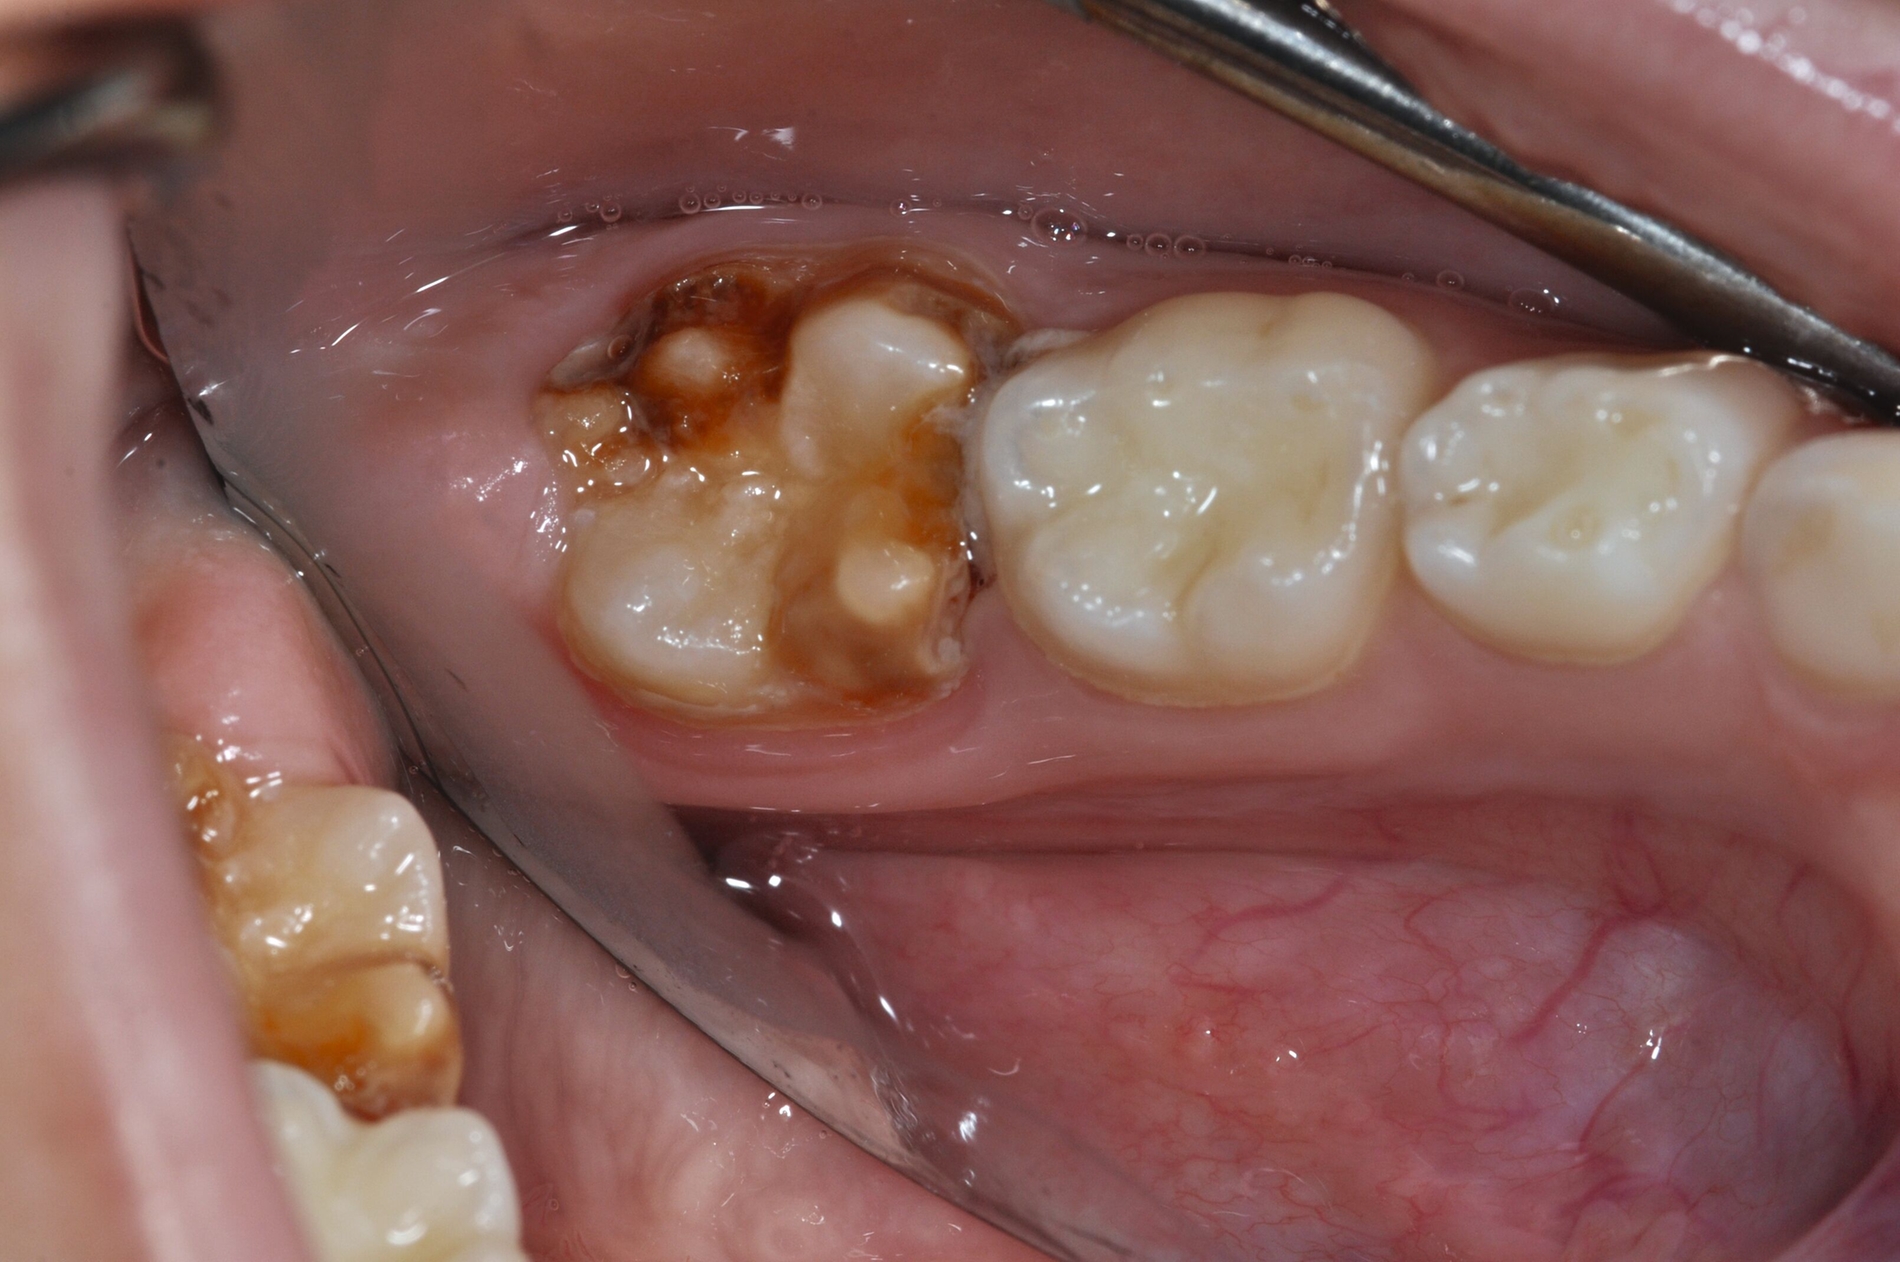

Die temporäre Therapie C (kurzfristig)

Die Therapie C hat das Ziel, MIH-Zähne vorübergehend zu versorgen, bis der vollständige Durchbruch der Zähne eine adhäsive Restauration ermöglicht, um die hypersensiblen Zähne zu desensibilisieren oder/und die Mitarbeit für die weitere Behandlung aufzubauen. Vor dem Hintergrund des erhöhten Kariesrisikos dieser Zähne (Abbildung 2) muss durch die Maßnahmen eine Kariesprogression vermieden werden.

Als mögliche Maßnahme steht eine Abdeckung der Defekte mittels konventioneller Glasionomerzemente (GIZ) zur Verfügung. Vorteil der Materialien ist die schnelle und einfache Applikation der Zemente. Bei MIH-Molaren werden diese in der Regel mittels der sogenannten ART-Technik (Atraumatic Restorative Treatment) eingesetzt [Grossi et al., 2018]. Dabei wird lediglich mit einem Handinstrument die Zahnoberfläche gereinigt und gegebenenfalls Karies exkaviert. Anschließend wird die Kavität unter relativer Trockenlegung mit dem GIZ aufgefüllt.

Der Vorteil der Methode ist, dass die betroffenen Zähne auch ohne Lokalanästhesie und Präparation versorgt werden können. Die temporäre Versorgung ermöglicht es, die Patienten an die zahnärztliche Behandlung zu gewöhnen. Häufig führt diese temporäre Versorgung auch zu einer Reduktion der Hypersensitivität der MIH-Zähne. Nachteil der GIZ-Versorgung ist das Risiko einer Füllungsfraktur oder eines vollständigen Verlusts der Füllung (Abbildung 4). Aktuelle Erhebungen bestätigen eine Erfolgsrate von über 80 Prozent nach einem bis zwei Jahren [Durmus et al., 2021; Mahfouz et al., 2025].

Der Behandlungsfall (Abbildung 4d) veranschaulicht die Schwächen des Verfahrens. Wird das Angebot der regelmäßigen Kontrollen nicht wahrgenommen, so droht bei Verlust der Füllung die Kariesprogression. In dem vorliegenden Fall konnte jedoch eine endodontische Maßnahme vermieden und durch die selektive Kariesentfernung die Zahnhartsubstanz weitestgehend erhalten werden.